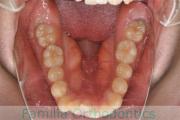

- ≫治療前

-

上顎

下顎

前歯の関係など

右側

正面

左側